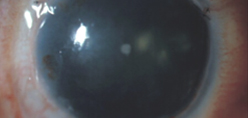

She said the first step, even before treatment, is to stage the disease. She uses live imaging to evaluate the stem cell function in these eyes. “We do anterior segment OCT first to look at the epithelial thickness in these eyes to make sure we don’t misdiagnosis the stem cell deficiency,” she said. “Subsequently, we will perform in vivo confocal microscopy on these eyes to look at the microstructure of limbus and cornea.” We come up with a formula to quantify the stem cell function, she said.

Dr. Deng said that we want our trainees to be exposed to various procedures and therapies. “The fellows and residents are here to get exposed to how we make the diagnosis, stage the disease, using multimodal in vivo imaging. First, the fluorescein straining pattern is carefully examined to detect stippling staining in a whorl-like pattern, Next, an anterior segment optical coherence tomography is performed to detect whether a hyporeflective epithelial layer is present on the cornea and limbus. Lastly, in vivo confocal microscopy is performed to evaluate whether corneal and limbal epithelial cells are present in high density.” These in vivo imaging tests are a fast way to make the correct diagnosis of LSCD, she said. “We also perform impression cytology to confirm presence of conjunctival cells on the cornea, which is the hallmark of limbal stem cell deficiency,” Dr. Deng said. “The trainees are exposed to the surgical techniques of limbal stem cell transplantation and amniotic membrane graft for partial deficiency. Our trainees here have well rounded exposure to the diagnosis and management of limbal stem cell deficiency.”